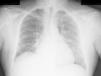

Miocardiopatía aguda como manifestación clínica de esclerosis sistémica

Acute cardiomyopathy as a clinical manifestation of systemic sclerosis